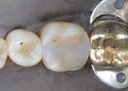

Matt Dodson #30 composite removal